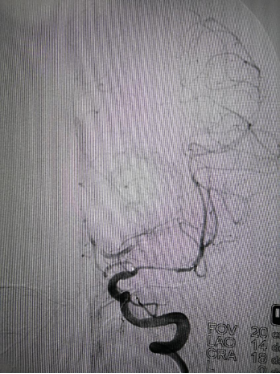

赛诺球囊扩张后狭窄有所改善但管壁不光滑

药物球囊扩张(2.0 mm×20 mm)

药物球囊扩张后

药物球囊扩张后10分钟狭窄明显改善且血管壁较光滑